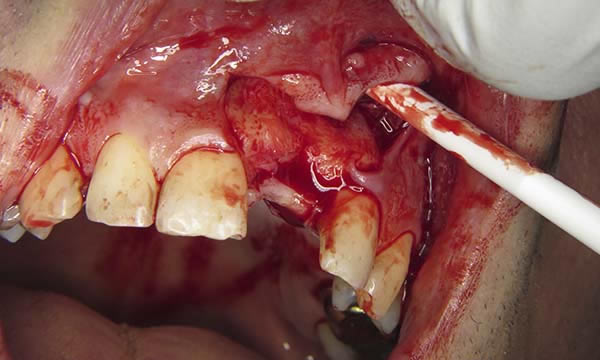

Case C

A case of a patient who was a long term resin retained bridge wearer. The resin retained bridge was placed after the patient lost his UL1 many years ago. There was a history of the resin retained bridge lute failing, and due to the loss of the UL1 there was a labio - palatal bone deficit.

A clear acrylic position guide was used to guide implant placement within the aesthetic envelope and guided bone regeneration was used labially to elevate the long standing concavity. A Bonded crown was used to restore the implant and at the 12 month follow up, the bone level around the implant remains unchanged and the patient is confidently smiling.

During Treatment